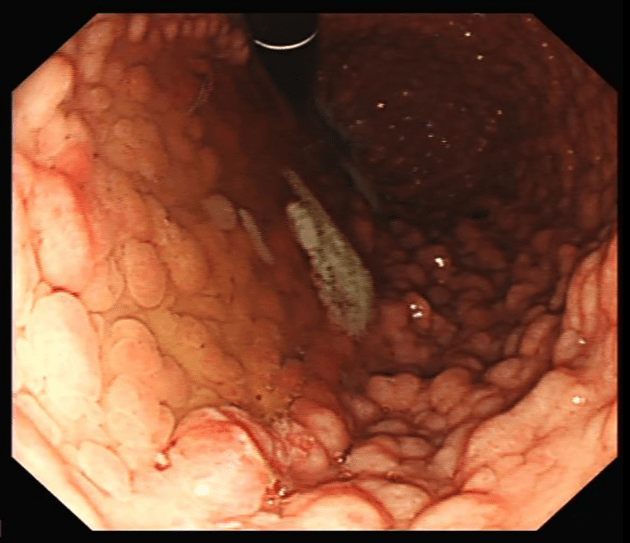

Endoscopic Images and IPAA Anatomy:

Figure 1

Figure 1: